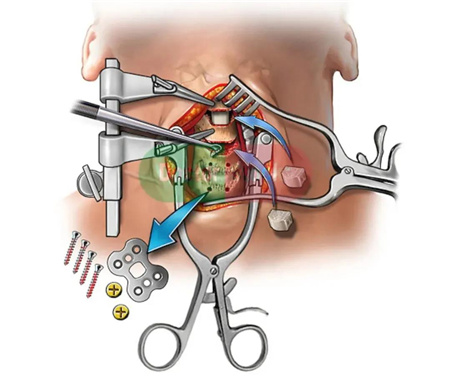

颈椎前路手术、颈椎后路手术、前后路联合手术等。